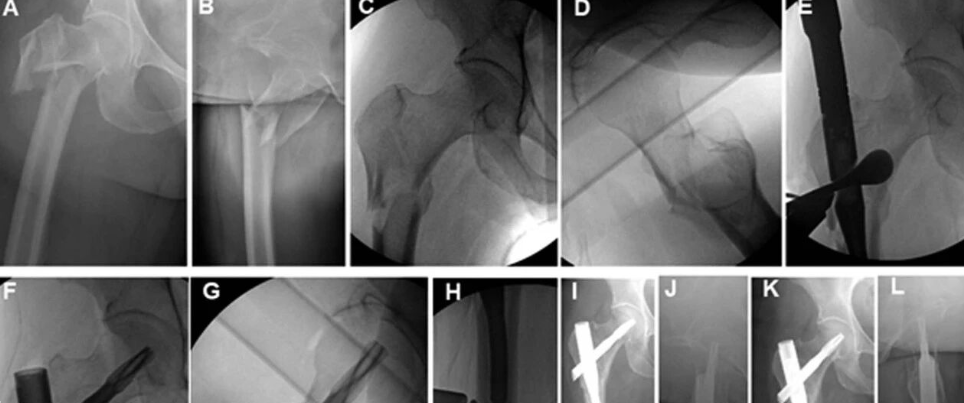

图1. 使用(A、B)Hintermann牵开器或(C、D)点氏复位钳恢复腓骨的长度、旋转和角度。

图2. 术中展示了Hintermann牵开器的放置(A)以及腓骨髓内(IMF)钉导针的置入(B、C)。Hintermann牵开器应将闭合的臂放置在腓骨的前半部分或后半部分,以便为髓内钉的插入留出空间。用于导针放置、扩髓和髓内钉的插入。

图3. 术中系列展示了髓内钉钉的放置。肢体向内旋转(A)以在术中透视(B)下达到 “中心-中心” 位置,此时腓骨在胫骨内居中对齐。在保持肢体位置的同时,旋转髓内钉本身,直到下胫腓联合孔完全对齐,然后连接外支架导向器。用2枚临时克氏针固定来维持这个位置。然后通过直接触诊前方远端胫腓骨的对合情况来验证下胫腓联合的重新对线(C)。这种技术避免了术中评估下胫腓联合复位时固有的主观性和困难。

图4. 三踝骨折采用微创方法修复,内踝骨折采用经皮螺钉置入,腓骨骨折采用髓内钉。展示了外侧(A)和内侧(B)经皮小切口。术后负重位X线片(C、D)显示内固定下的踝关节骨折初步愈合。